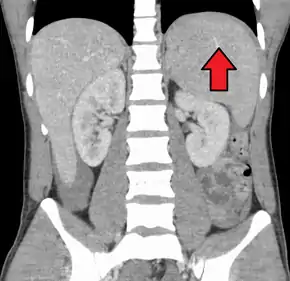

Spleen enlargement is common in the second and third weeks, although this may not be apparent on physical examination. Rarely the spleen may rupture.[24] There may also be some enlargement of the liver.[22] Jaundice occurs only occasionally.[14][25]

Splenomegaly is a common symptom of infectious mononucleosis and health care providers may consider using abdominal ultrasonography to get insight into the enlargement of a person's spleen.[57] However, because spleen size varies greatly, ultrasonography is not a valid technique for assessing spleen enlargement and should not be used in typical circumstances or to make routine decisions about fitness for playing sports.[57]